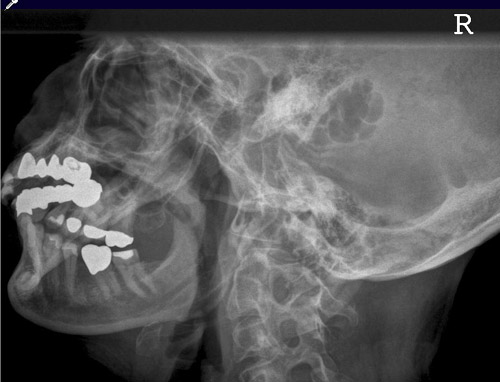

Schädel a.p.

44_2.jpg

Fehler

Schräge Projektion, d.h. ungleicher Seitenabstand der Schädelkapsel vom Keilbeinflügel.

Abhilfe

Symmetrische Lagerung des Kopfes.